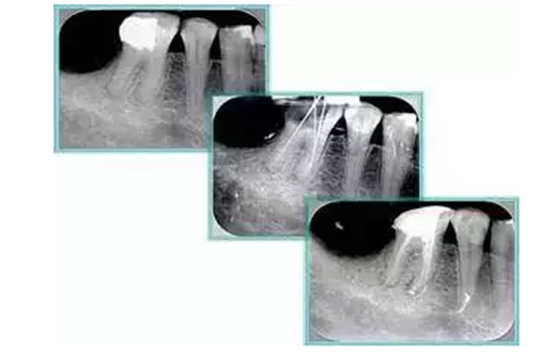

6. 鈣化

常見有修復(fù)性鈣化和增齡性鈣化。下面為根管鈣化 X 線片。

7. 器械折斷

右圖及下圖為器械折斷的 X 線片。箭頭處示折斷器械。

解決方法: ( 1 )取出。 ( 2 )通過。 ( 3 )重新確定工作長度,充填。 ( 4 )根尖手術(shù)。

器械折斷可以不用取出,取出的原因多是患者心理因素。留在里面的器械關(guān)鍵是進(jìn)行消毒,預(yù)防性使用抗感染藥物,預(yù)防感染。